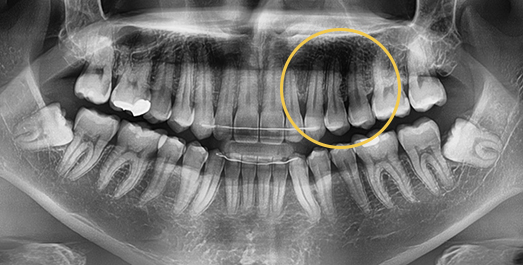

Impacted Tooth Solution

An impacted tooth remaining within the alveolar bone can cause damage to adjacent teeth. Orthodontic traction is used to guide the impacted tooth into its correct position,

allowing it to erupt and seat normally within the dental arch.

• BEFORE: 2011.08.12

• AFTER: 2013.07.08